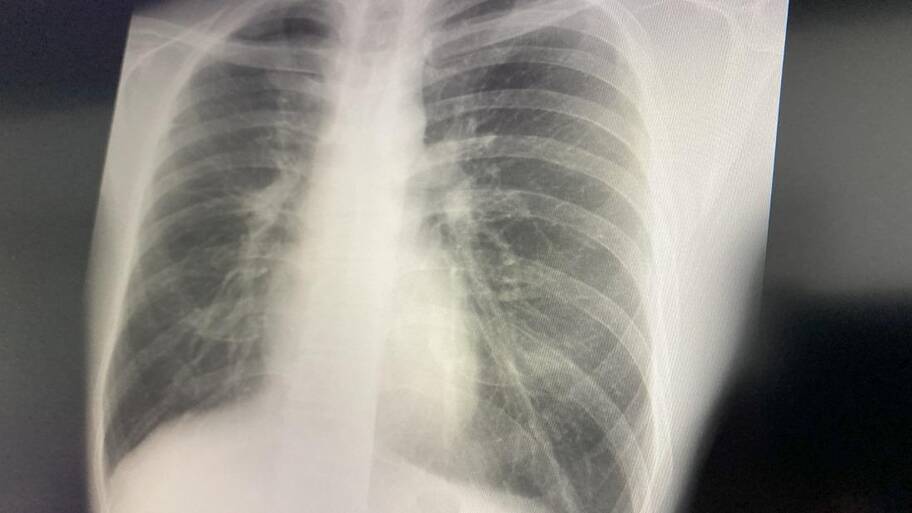

写真:maroke/イメージマート